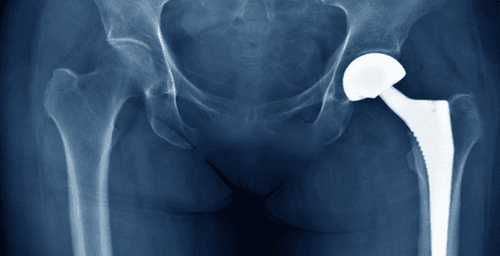

Một điều tai hại nữa của căn bệnh oái oăm này là: bệnh xuất hiện rất từ từ, thầm lặng. Người bệnh ban đầu chỉ cảm thấy mỏi hoặc đau rất mơ hồ vùng hông; nằm nghỉ thấy đỡ đau; chẳng thấy liên quan gì đến rượu. Có người cho rằng mình bị "bệnh thấp khớp", cũng chịu khó "đông tây y kết hợp" và thấy đỡ đau. Sau đó vài ba tháng đột nhiên đau dữ dội từ bẹn xuyên ra sau mông, khẽ nhúc nhích chân cũng đau, uống rượu vào càng đau hơn. Chụp phim X-quang thấy chỏm xương đùi bẹp dúm, méo mó. Chẳng còn cách nào cứu vãn tình thế. Đành phải mổ cắt bỏ phần khớp bị hỏng, thay bằng một bộ khớp nhân tạo.

Khi phát hiện bệnh ở giai đoạn I, II bác sĩ phẫu thuật có thể khoan giảm áp lõi chỏm để tăng tưới máu cho vùng chỏm bị "khô hạn". Phẫu thuật này rất nhẹ nhàng: chỉ cần rạch da khoảng 2 cm, định vị vùng hoại tử dưới màn tăng sáng, khoan một đường hầm dẫn máu từ phía mấu chuyển lớn qua cổ xương đùi vào lõi chỏm, tới tận vùng bị hoại tử. Bệnh nhân sẽ cảm thấy nhẹ nhõm ngay sau mổ. Trên 80% số chỏm hoại tử giai đoạn I, II được cứu sống, không phải mổ thay khớp. Tất nhiên bệnh nhân phải cai rượu và thuốc lá. Không may bệnh đã đến giai đoạn III - giai đoạn "rất tế nhị": vì khoan giảm áp gây hỏng thêm, ghép xương, tủy xương cho kết quả rất bấp bênh, thay khớp thì sớm quá, trong khi tình trạng đau của bệnh nhân có phần đỡ đi. Nhiều bác sĩ chỉ cho thuốc uống và chờ đợi, nếu bệnh chuyển sang giai đoạn IV (đau tăng, cứng khớp) thì chỉ định mổ thay khớp.

Mặc dù các loại khớp nhân tạo hiện nay ngày càng được cải tiến, có khả năng đáp ứng cho các loại bệnh lý, có độ bền tốt hơn, song thay khớp háng nhân tạo ở người trẻ tuổi vẫn còn nhiều vấn đề nan giải. Muốn có được kết quả chắc chắn, thủ thuật thay khớp nhân tạo nên để cho các phẫu thuật viên dày dạn kinh nghiệm thực hiện. Tất nhiên các phẫu thuật viên có đủ kinh nghiệm cũng cần phải được trang bị cả "một kho vũ khí hiện đại hoàn chỉnh" để đối phó với mọi vấn đề phát sinh trong quá trình phẫu thuật lắp đặt khớp nhân tạo.